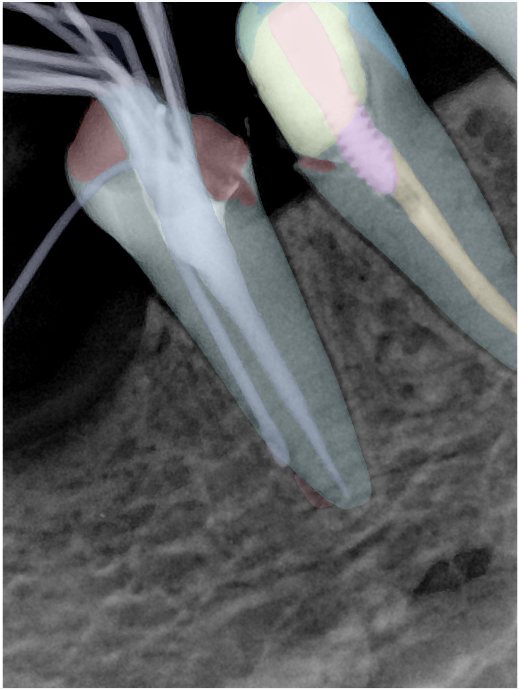

CR/DR 牙齿分割阶段记录

当前进展

- 完成了 CR/DR 牙齿相关分割训练

- 当前结果已经达到阶段预期,但仍有细节问题需要继续处理

相关测试

遇到的问题

- 训练过程中出现过 mask 下移问题

- 部分结果会出现 box 填充异常

- mask 边缘仍然有比较明显的锯齿感

参考

第二版算法问题测试

第三版算法分辨率效果比较

| 编号 | 原图 | 第一版 | 第二版 | 第三版 1216x1600 | 第三版 768x1024 | 第三版 1120x1120 |